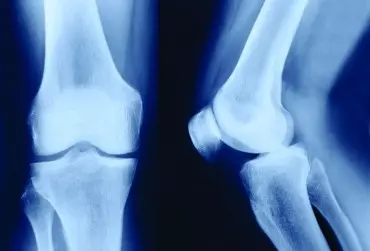

Artroskopowa rekonstrukcja więzadła krzyżowego przedniego zasady fizjoterapii

Urazy miękkich elementów stawu kolanowego są problemem dość często spotykanym w gabinetach fizjoterapeutycznych. Tego typu urazom sprzyjają wszelkiego rodzaju sporty zimowe oraz football. Poza sportowcami urazy tkanek miękkich dotyczą często również ludzi nieaktywnych fizycznie czy osób starszych. Jednym z urazów jest zerwanie więzadła krzyżowego przedniego.

Wybrane metody fizykalne w terapii stawów kolanowych z patologią łąkotkową leczonych artroskopowo

Szacuje się, że obrażenia stawu kolanowego stanowią 15–30% wszystkich uszkodzeń ciała, w urazach sportowych odsetek ten wzrasta od 33–70%. Wykluczając sportowców, urazy tkanek miękkich dotyczą często również osób nieaktywnych fizycznie i osób starszych [1–3].